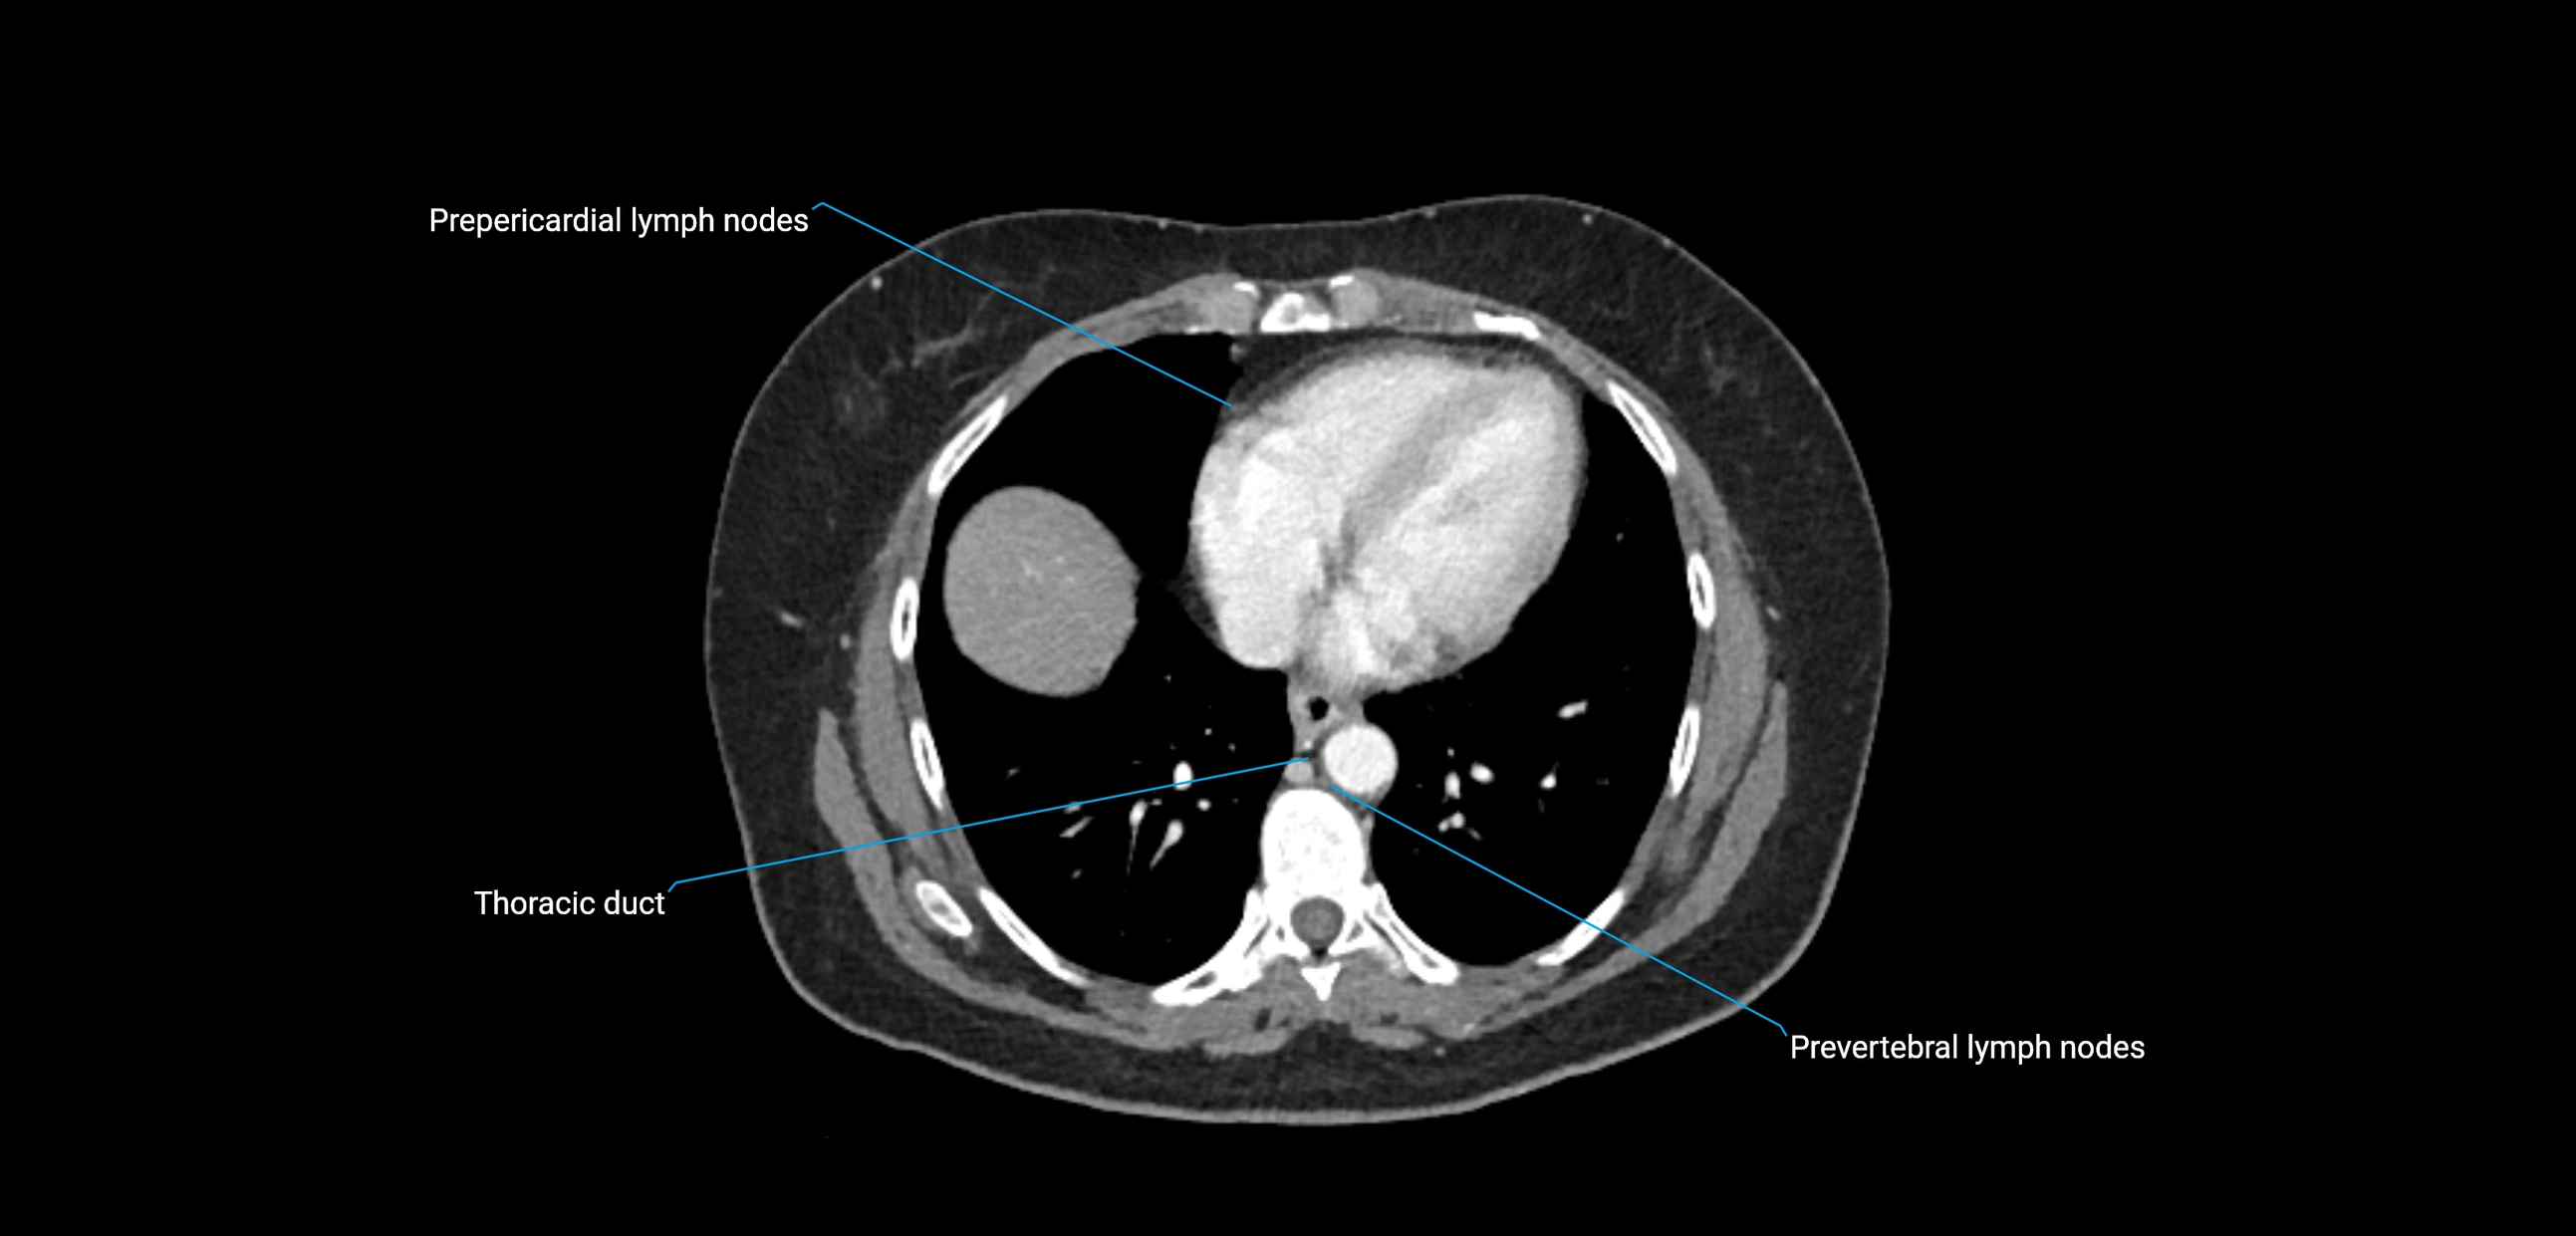

CT image

image